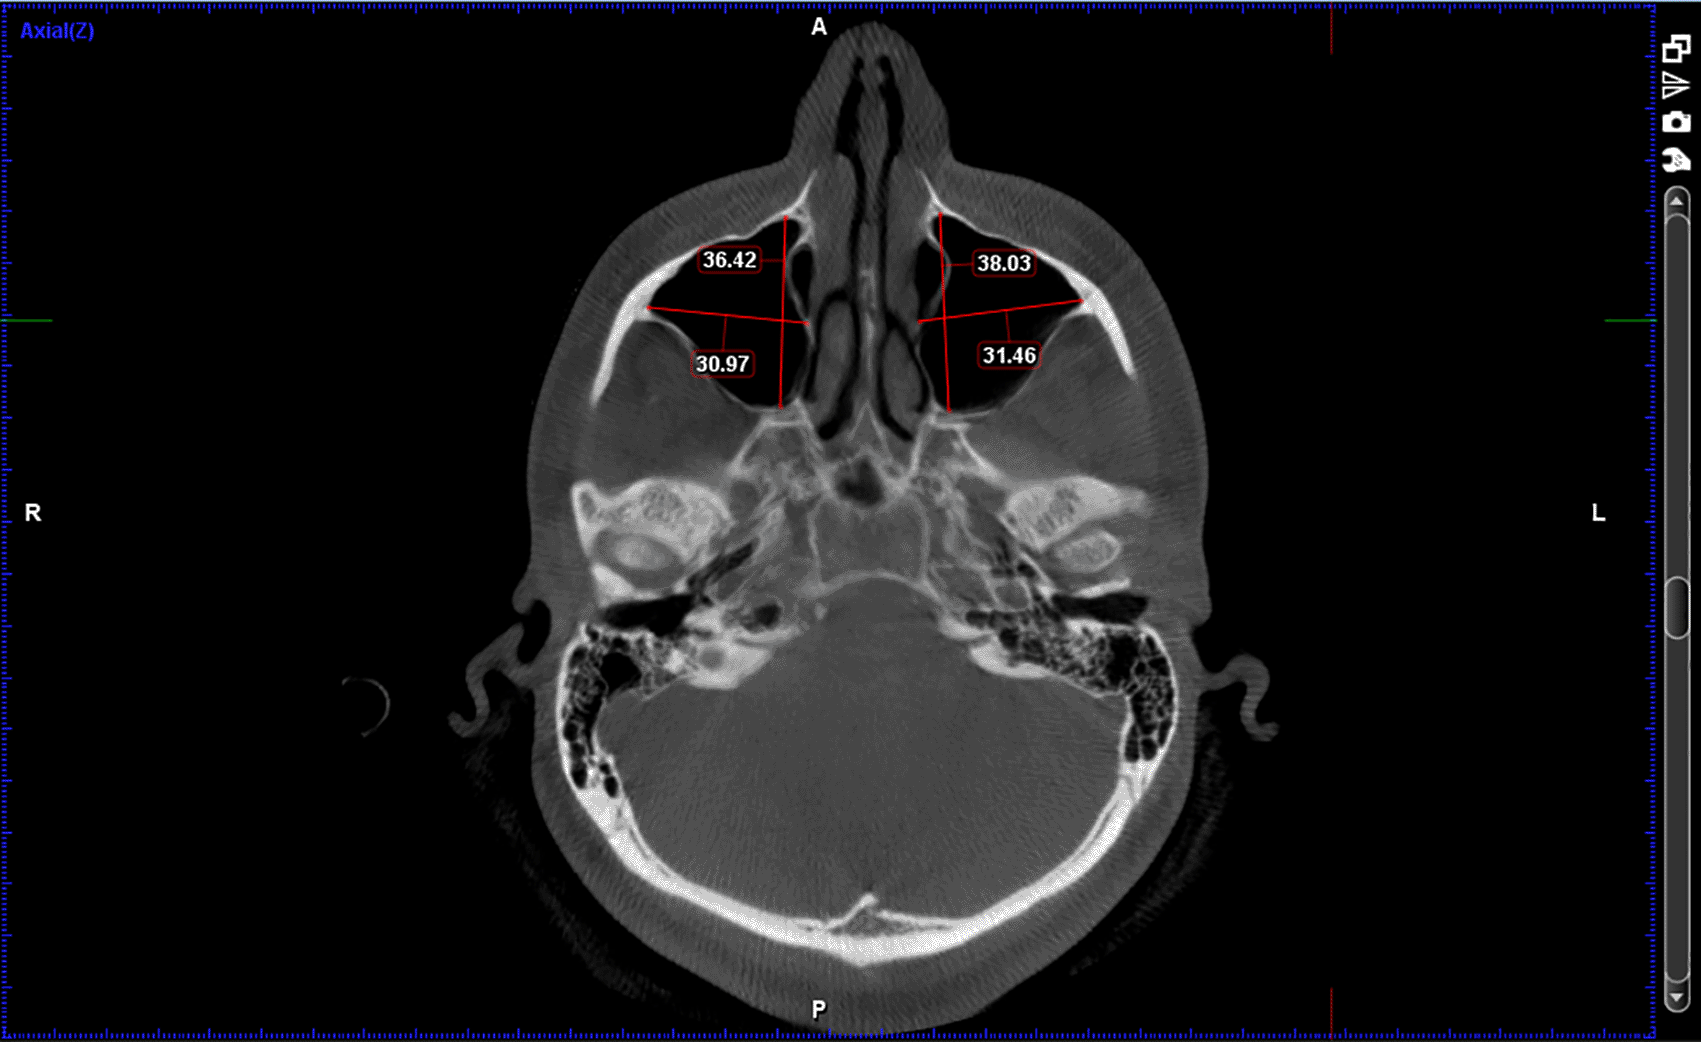

A total of 66 full FOV CBCT scans of patients satisfying inclusion and exclusion criteria were collected from the department archives. The CBCT images were previously obtained with patients written consent for diagnostic purpose using Planmeca ProMax Machine (230-240 V, 50 Hz, 16 A) manufactured by Planmeca OY (Helsinki Finland). The images were in DICOM file format and were analysed using Planmeca Romexis Viewer (Version 5.1.0.4). All the records were analysed by a single observer. Three locations were chosen to measure sinus height and basal bone height: PM1-PM2(between premolars), PM2-M1(between 2nd premolar and 1st molar), M1-M2(between molars).

Following measurements were recorded bilaterally and mean value was obtained; Figures: 1-3

3. Width of the maxillary sinus

4. Depth of maxillary sinus